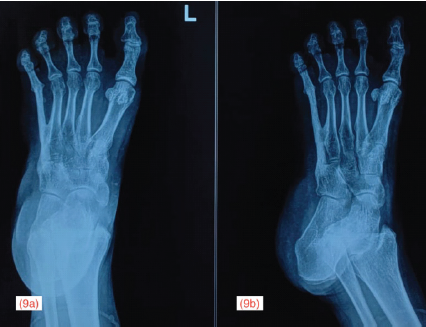

She was allowed partial weight bearing after 3 months and full weight bearing after 5 months. At the final follow-up of 2 years, the patient was walking with full-weight bearing without pain. Ankle movements were from 20° of plantar flexion to 10° of dorsiflexion, which was pain-free, but there was restriction of inversion and eversion. Fig. 9 shows the radiograph and Fig. 10 shows the clinical function of the patient at final follow-up. The patient was able to perform activities of daily living without significant pain or major functional deficit, demonstrating a successful outcome of the limb salvage procedure.

Figure 9: Final follow-up at the end of 2 years, showing radiograph of left foot in anteroposterior (a) and oblique (b) view, showing good incorporation of the hemifibula autograft